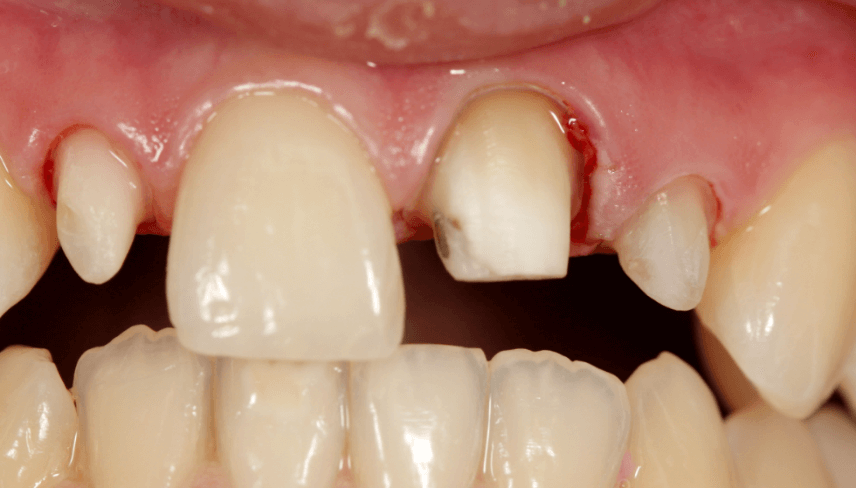

3. Fogkorona előkészítése, lenyomatvétel

Attól függően, hogy koronát, hidat vagy fix, illetve kivehető pótlást kell alkalmazni, változhat a kezelés első fázisa. Korona és híd esetében a fog(ak) előkészítése – csiszolás -, a lenyomat- és harapásvétel és az ideiglenes korona/híd behelyezése ilyenkor történik, helyi érzéstelenítésben. A fogszín meghatározása is ekkor történik.